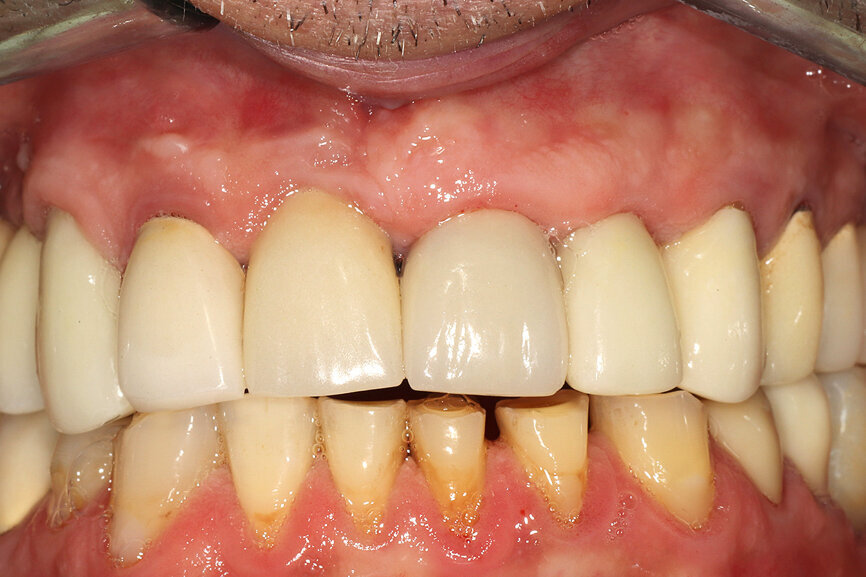

Fig. 12a: A post fracture presenting in the left central incisor, requiring extraction.

Fig. 12b: The occlusal view illustrated the cervical tissue volume and contours.

A 62-year-old male patient presented with a hopeless prognosis for a post fracture in the left central incisor requiring extraction (Figs. 12a & b). The preoperative periapical radiograph revealed an existing implant supporting a metal–ceramic restoration for the adjacent region #11 (Fig. 13). The CBCT (CS 9600, Carestream Dental) cross-sectional image revealed a favourable preoperative condition relating to the trajectory of the endodontically treated root to the alveolus for a PET procedure (Fig. 14a). Using the native Carestream 3D Imaging software, a simulated implant and abutment projection was positioned within the available bone to avoid the root fragment (Fig. 14b).